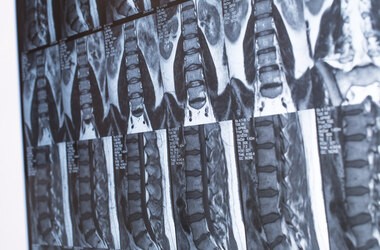

Diagnostyka dyskopatii kręgosłupa opiera się na badaniu fizykalnym oraz wykonaniu zdjęcia rentgenowskiego (RTG kręgosłupa). W niektórych przypadkach lekarz decyduje o poszerzeniu zakresu badań, wówczas zleca tomografię komputerową, rezonans magnetyczny kręgosłupa, a w przypadku zaburzeń czucia, osłabienia mięśni – badanie EMG.